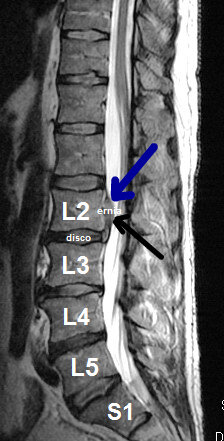

Il paziente presentava da 2 mesi dolore lombare con irradiazione alla coscia e ginocchio sinistro, del tipo cruralgia con associate intense parestesie (formicolii).

L’obbiettività neurologica evidenziava ipotonia del muscolo quadricipite femorale di sinistra.

Una risonanza lombare evidenziava un’ernia discale espulsa L2-L3 sinistra e migrata verso l’alto.

Le terapie farmacologiche avevano prodotto solo un parziale e non significativo miglioramento del dolore.

Il paziente optava per trattamento conservativo con ossigeno-ozono terapia.

Già dopo la seconda seduta, il signore beneficiava di un miglioramento della sintomatologia dopo 6 sedute di ozonoterapia e nel giro di 5 settimane recupero completo dell’autonomia lavorativa.

Dopo pochi mesi il signore ha potuto riprendere l’attività sportiva non agonistica.

A distanza di 12 mesi ha effettuato una nuova risonanza magnetica lombare, che ha documentato la completa scomparsa dell'ernia.

Per questo e numerosi altri casi documentati, vale sempre la non certezza della correlazione tra ozonoterapia ecoguidata e regressione dell'ernia.